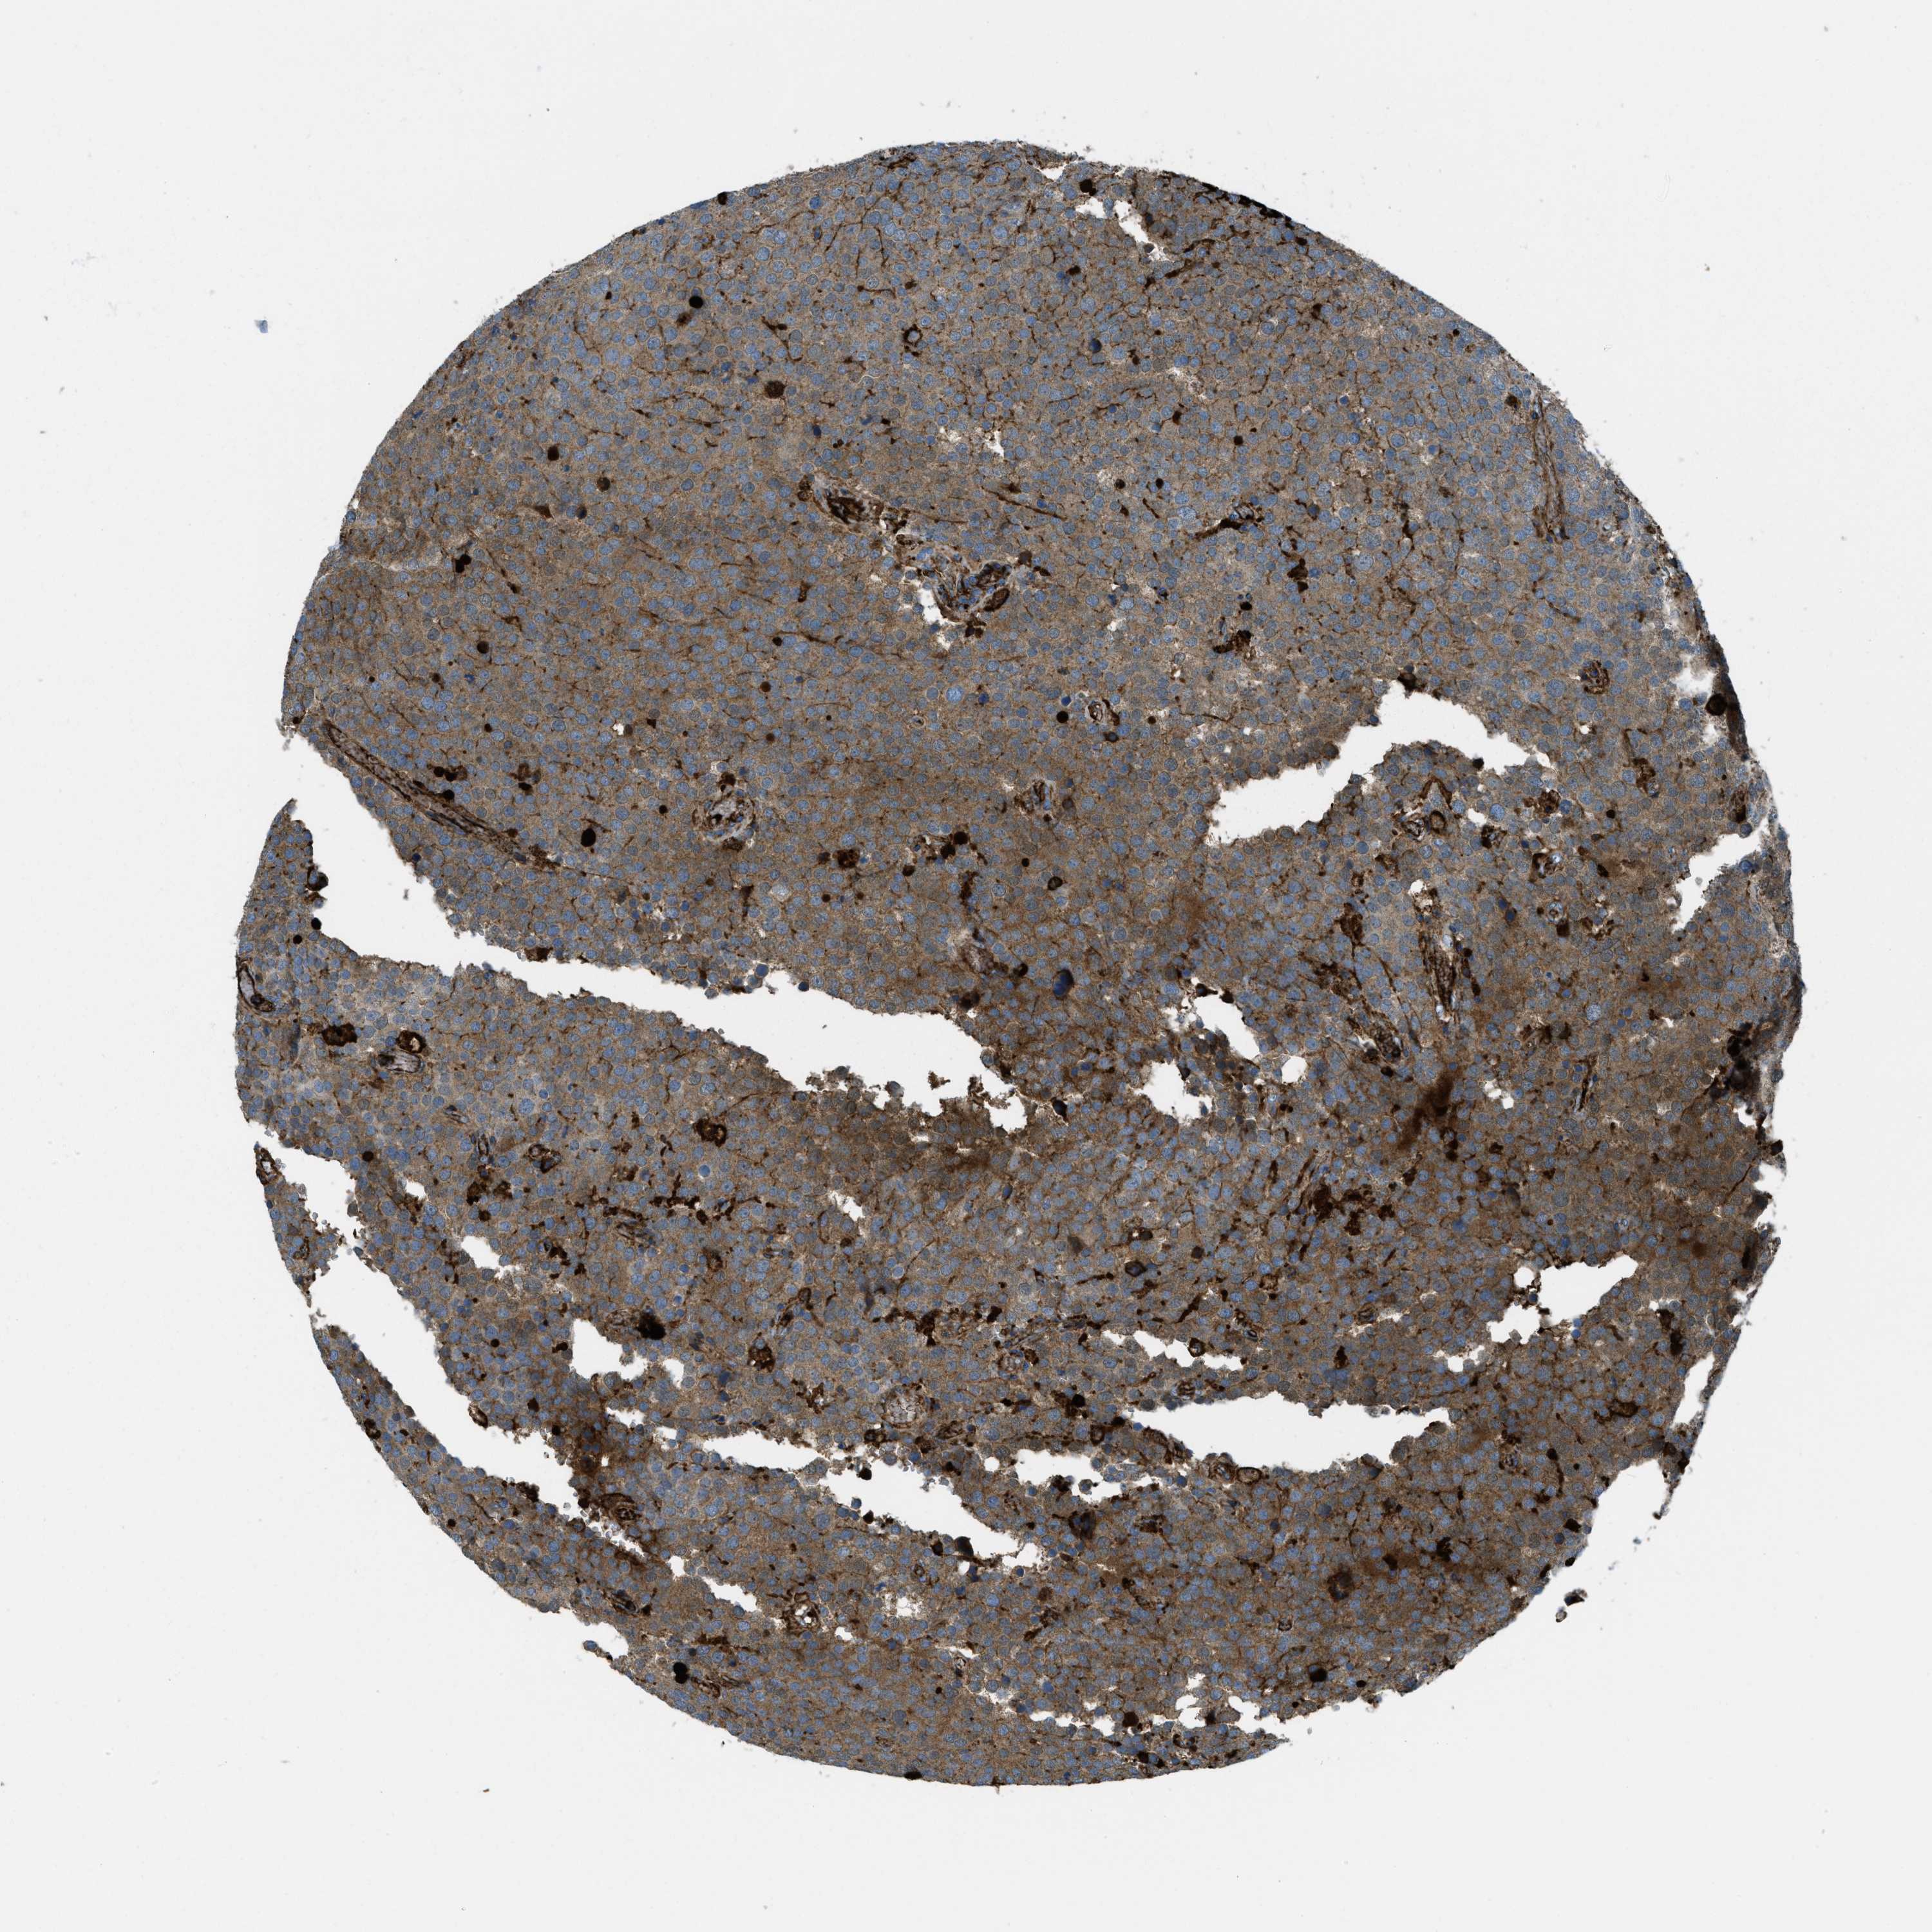

TESTIS CANCER - Protein expressioni

A mouse-over function shows sample information and annotation data. Click on an image to view it in a full screen mode. Samples can be filtered based on level of antibody staining by selecting one or several of the following categories: high, medium, low and not detected. The assay and annotation is described here.

Note that samples used for immunohistochemistry by the Human Protein Atlas do not correspond to samples in the TCGA dataset.

Antibody stainingi

Antibody staining in the annotated cell types in the current human tissue is reported as not detected, low, medium, or high, based on conventional immunohistochemistry profiling in selected tissues. This score is based on the combination of the staining intensity and fraction of stained cells.

Each image is clickable and will lead to virtual microscopy that enables deeper exploration of all samples and also displays staining intensity scores, fraction scores and subcellular localization as well as patient and tissue information for each sample.

Antibody HPA017750

Staining

High

Medium

Low

Not detected

Intensity

Strong

Moderate

Weak

Negative

Quantity

>75%

75%-25%

<25%

None

Location

Nuclear

Cytoplasmic/membranous

Cytoplasmic/membranous,nuclear

Carcinoma, Embryonal, NOS

Seminoma, NOS